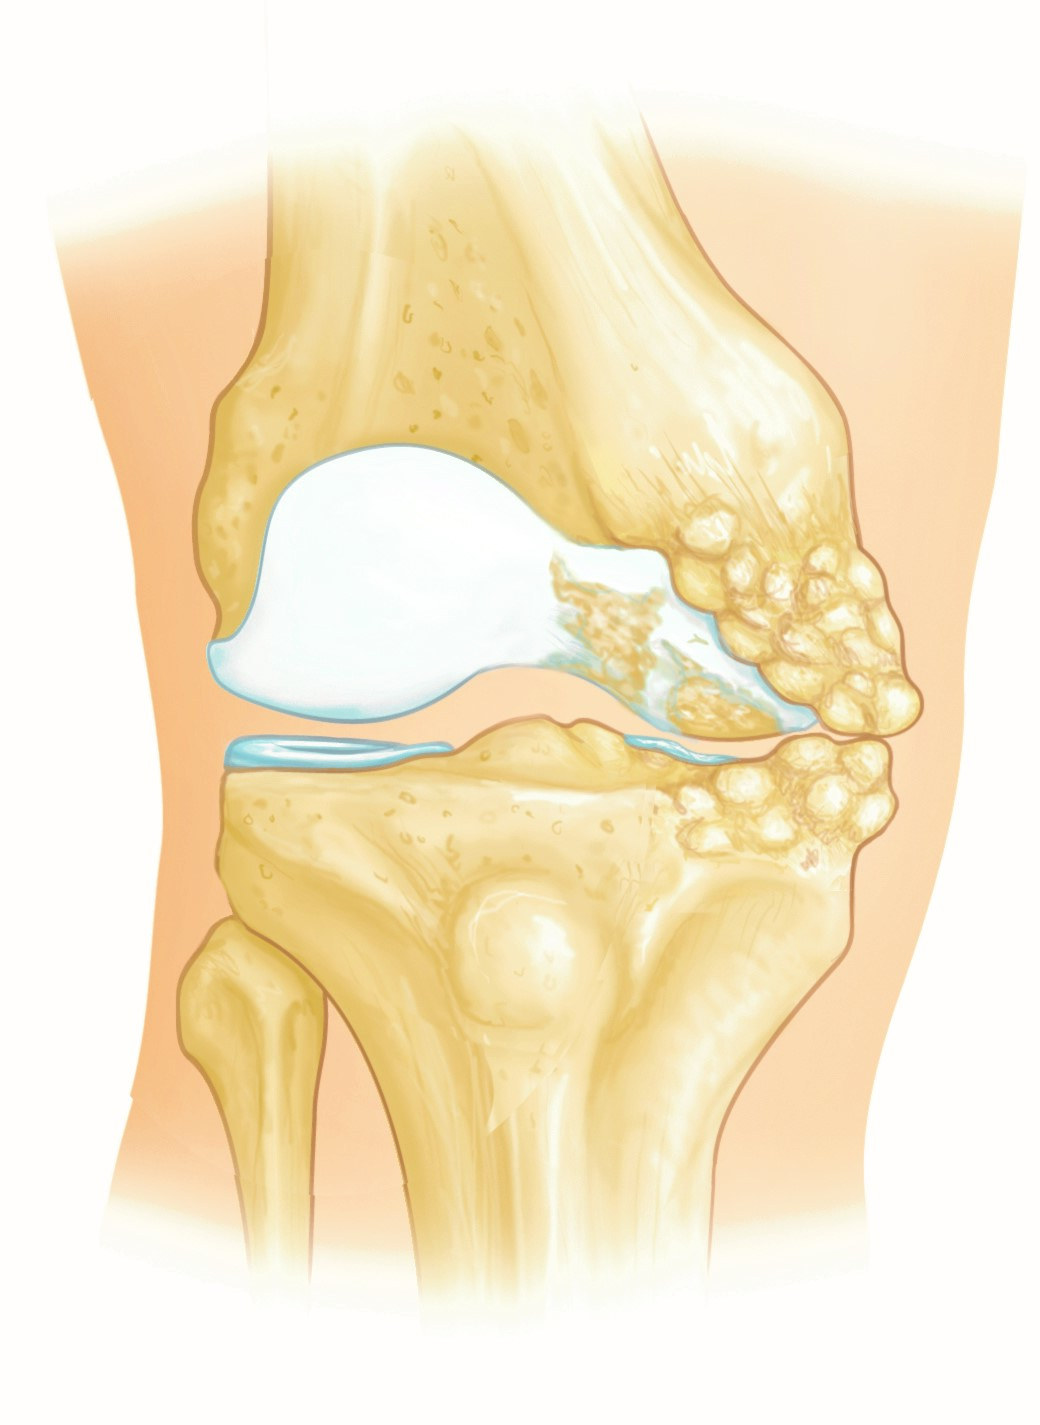

Knee Joint

The knee is a hinge joint made of the lower thighbone (femur), the upper shinbone (tibia), and the kneecap (patella). The ends of these bones are covered with articular cartilage, which is a smooth tissue that cushions the ends of the bones. This allows the joint to move easily.

The menisci are C-shaped structures located between the femur and tibia. They act as shock absorbers to cushion the joint.

Large ligaments (the cruciates and collaterals) hold the femur and tibia together and provide stability. The long thigh muscles (the quadriceps and hamstrings) give the knee strength.

A thin tissue called the synovial membrane surrounds the knee joint. In a healthy knee, this membrane makes a small amount of fluid that lubricates the cartilage and eliminates almost all friction during knee movement.

In hip and knee arthritis, the cartilage protecting the bones of the knee wears away. This can occur throughout the joint or just in a single area. Joint replacement is the surgical treatment for advanced arthritis.